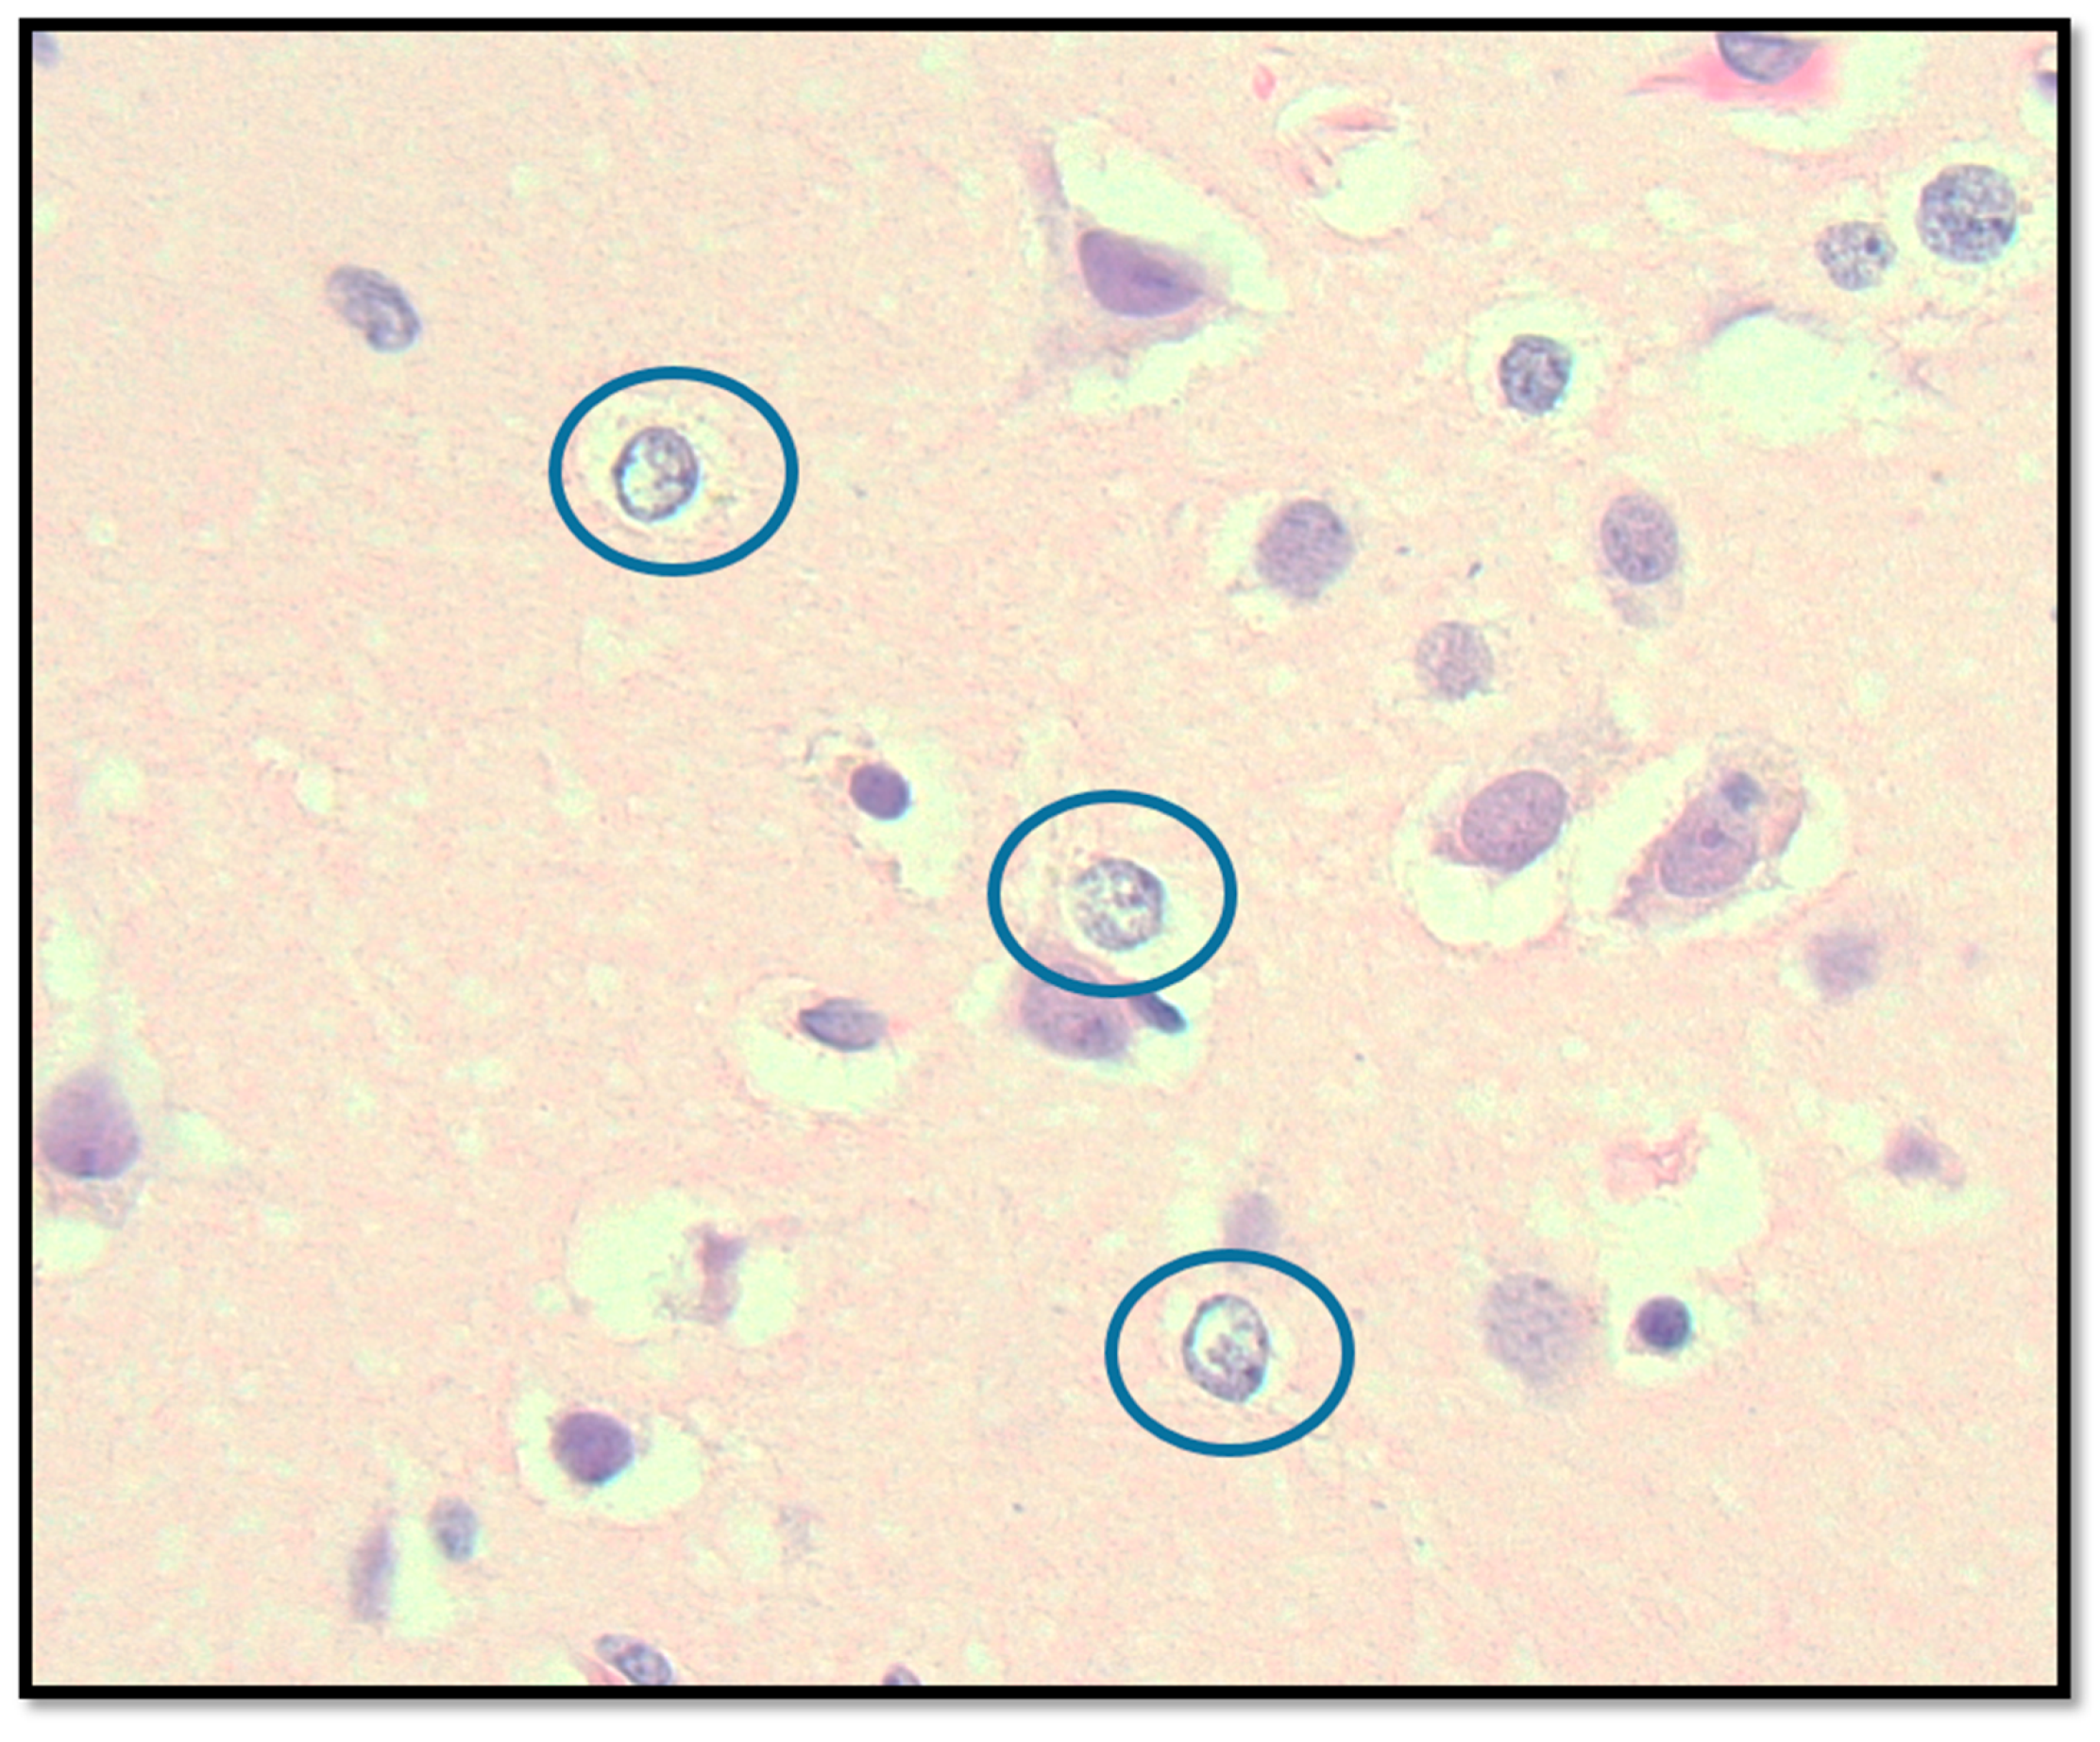

2.3.2. Central Nervous System Findings

3.5. Suspicion of Mitochondrial Involvement in This Patient with Advanced hEDS